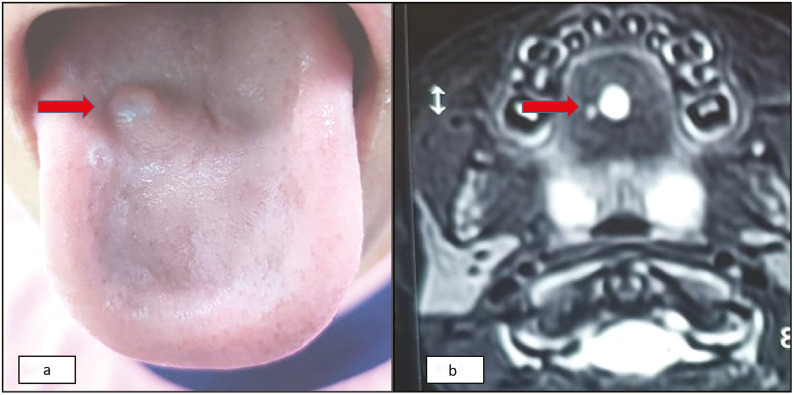

前肠重复囊肿是一种罕见的先天性异常,可以发生在胃肠道的任何地方,包括舌头。通常通过影像学检查诊断;很少进行吸痰细胞学检查。细针吸细胞学(FNAC)可以帮助区分前肠重复囊肿与其他类型的舌性病变,如皮样囊肿、淋巴管瘤或恶性肿瘤。本报告描述了一名7岁女孩的FNAC检查结果,她在过去的5个月里出现了舌头背侧无痛性肿胀。

Foregut duplication cysts are rare congenital anomalies that can occur anywhere along the gastrointestinal tract, including the tongue. They are usually diagnosed by imaging studies; rarely, aspiration cytology is performed. Fine needle aspiration cytology (FNAC) can help to differentiate foregut duplication cysts from other types of tongue lesions, such as dermoid cysts, lymphangiomas, or malignancies. Present report describes FNAC findings of this condition in a seven year old girl who presented with a painless swelling on the dorsal aspect of her tongue for the past 5 months.